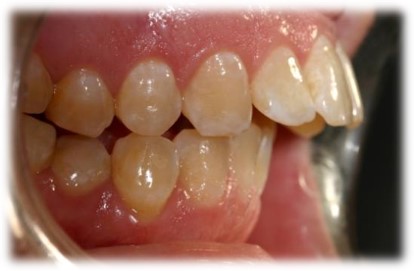

מנשך תקין

מנשך שבו השיניים בלסת העליונה ובלסת התחתונה,נפגשות האחת מול השנייה(ראה תמונות מצורפות).